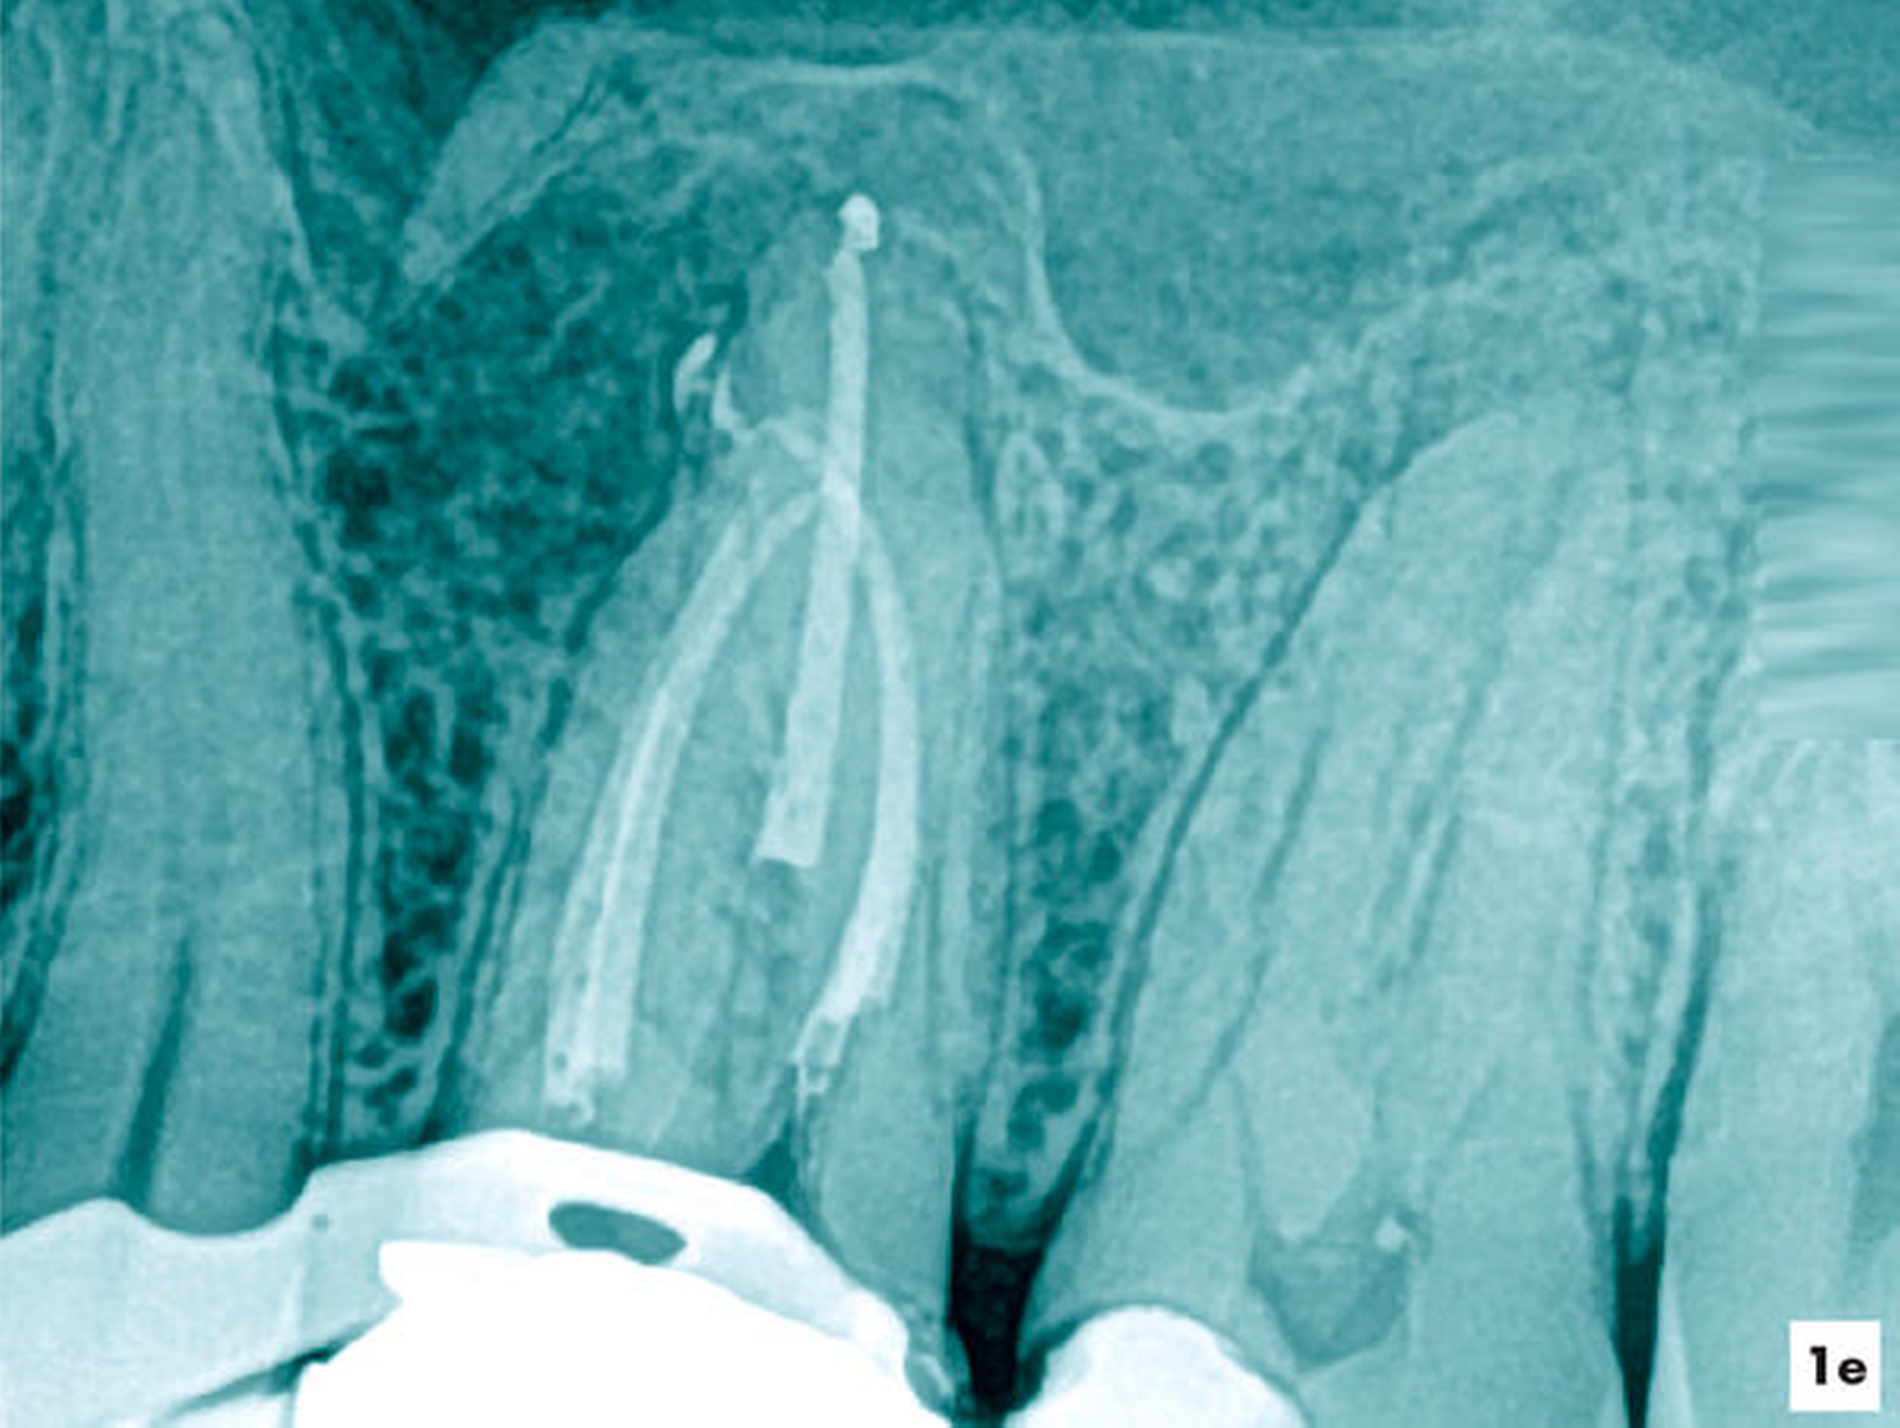

Fallbeispiel 2 (Abbildung 2)

Eine ehemals profunde Karies führte über mehrere Jahre zu einer degenerativen Pulpaerkrankung am Zahn 36. Röntgenologisch ließ sich eine Obliteration der Pulpakammer und des mesialen Wurzelkanalsystems erkennen. Distal lag eine periapikale Aufhellung vor, die klinisch mit einer Fistel assoziiert war (Abbildung 2a).

Unter absoluter Trockenlegung des Zahnes 36 mit Kofferdam erfolgte die Entfernung der Füllungsmaterialien. Im Verlauf der intrakoronalen Befundaufnahme und Diagnostik ließ sich bei 8- bis 16-facher Vergrößerung dunkel verfärbtes Dentin distal erkennen (Abbildung 2b). Innerhalb der Pulpakammer ließ sich ein dentinähnliches Hartgewebe zum Sekundärdentin differenzieren. Weichgewebige Einschlüsse am Rand ließen vermuten, dass es sich um eine reizgebundene Hartgewebeneubildung der Pulpa handelte (Abbildung 2c). Mit grazilen Rosenbohrern in absteigender Größe von ISO 012 bis 005 ließ sich das Hartgewebe sicher entfernen, so dass die mesialen Wurzelkanaleingänge für eine mechanische Erweiterung zugänglich waren (Abbildung 2d).

Während sich mesial vitales Pulpagewebe erhalten konnte, lag distal eine Pulpanekrose vor. Als Folge der Reizdentinbildung kam es auch in der distalen Wurzel zu einer Unterteilung in drei Wurzelkanäle, die bei 16-facher Vergrößerung substanzschonend erweitert, desinfiziert und gefüllt werden konnten (Abbildung 2e).

Zwei Tage nach Abschluss der einzeitigen Therapie war die Fistel verschlossen und zum 6-Monats-Recall ließ sich bereits eine deutliche Verringerung der periapikalen Aufhellung nachweisen (Abbildungen 2f und 2g).